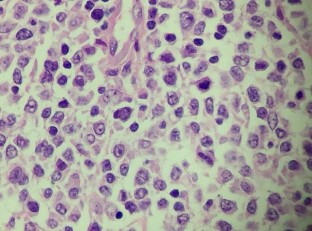

(Bệnh nhân : Hoàng Đình T.)

HE x 100: Tế bào u hình thoi, nhân lớn, rõ hạt nhân | HE x 400: U giàu nhân chia, bài tương giàu hạt sắc tố |

HE x 400: U giàu nhân chia, bài tương giàu hạt sắc tố | CHE x 400: U xâm nhập mạch bạch huyết |